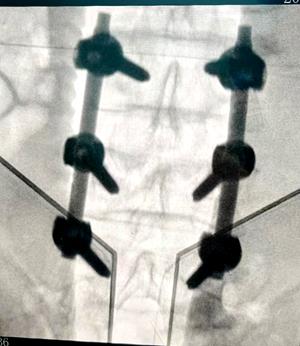

切开复位钉棒系统内固定术(正、侧位)放射影像(传统开放式手术)

该术式通过手术切开暴露骨折部位,将移位的椎体复位后,采用钉棒系统(螺钉+连接棒)对脊柱进行刚性固定,重建脊柱的稳定性,为骨折愈合和神经功能恢复创造条件。